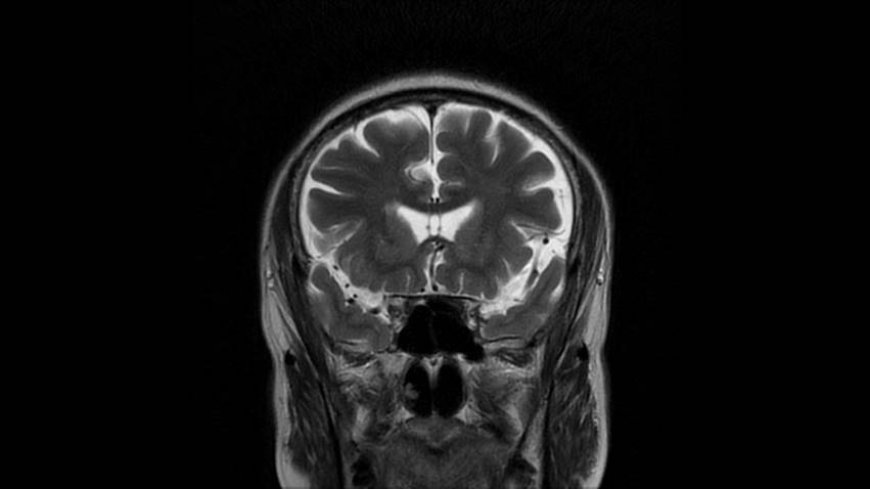

MRI of Brain

Coronal T2